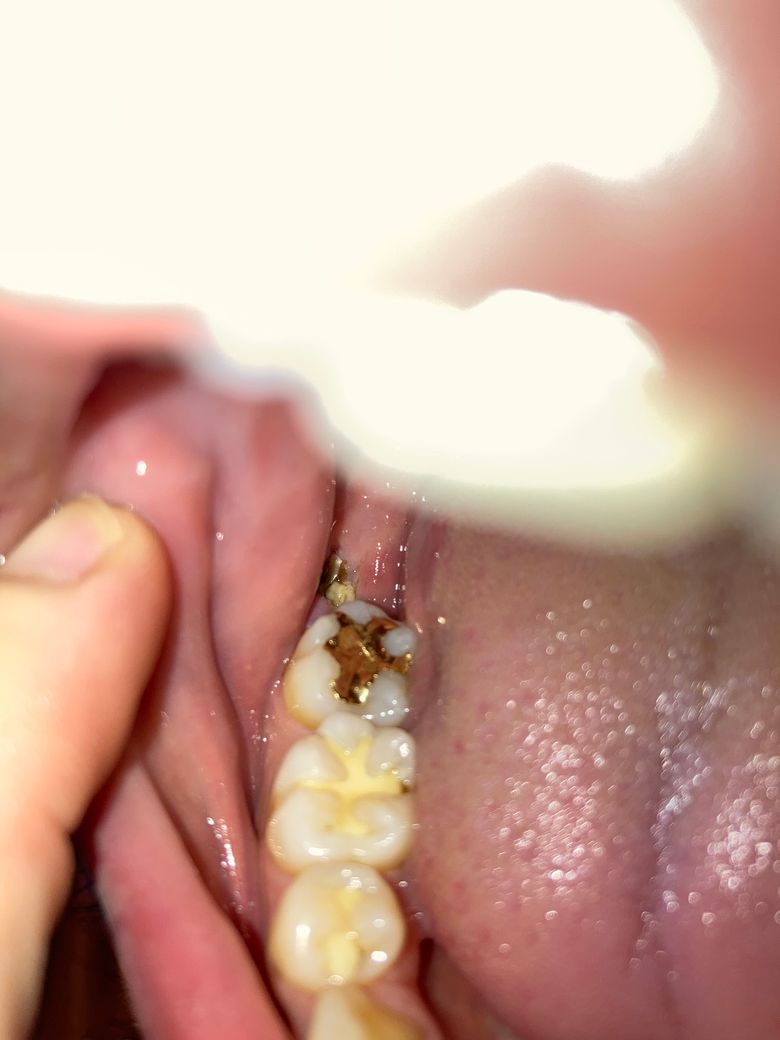

사랑니 발치 5일차 잘 회복중인 건가요?

5일 전 양쪽 사랑니 발치했습니다. 매복은 아니어서 봉합은 하지 않았습니다.

사진상으로 보았을 때 잘 아무는 중인지 판단 가능할까요?

• 2번 째 사진

사랑니를 발치한 후 해당 부위의 혈병이 완전히 형성되지 않은 것으로 보입니다 발치한 부위를 자극하지 않는 것이 좋습니다 발치를 한 부위는 자극을 하지 않는다면 일반적으로 2주 정도 지나면 아물게 됩니다.

사진상을 보면 크게 문제가 잇어 보이진 않습니다. 음식물등이 발치한공간에들어가 잇는상태이니 치과에 가셔서 소독한번 받아보시는게 좋을것같습니다.

사진상으로 발치부위가 잘 아무는 것으로 보이며, 해당부위에 염증이 덧나지 않도록 소독용 헥사메딘 가글액으로 가글하여 관리하길 권합니다.

1. 사진상으로 정확히 파악은 어려우나 별다른 증상이 없다면 큰 이상은 없는 것으로 보입니다.

2. 잇몸이 닫히는데는 2주정도 소요되고, 완전히 잇몸이 차오르기까지는 2달 정도 소요됩니다

3. 앞 어금니가 시린 것은 사랑니가 차지하고 있던 부분이 없어지면서 말하자면 어금니 옆구리가 드러나서 그렇습니다. 다시 잇몸이 차오르면 자연스럽게 시린 증상은 사라지나 지속적으로 불편하면 치과 가셔서 지각과민처치를 받으실 수 있습니다.